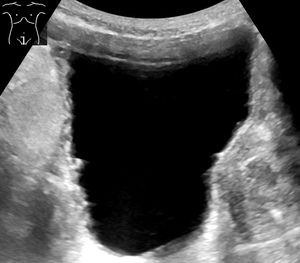

뇨류를 분석하면 배뇨 이상의 유형을 판단하는 데 도움이 될 수 있다. 방광 초음파를 통해 흔히 진단되는 것들로는 느린 속도의 뇨류, 간헐적인 뇨류, 배변 후에도 방광 내에 잔재하는 상당한 양의 오줌이 있다. 정상 시험 결과는 초당 최고 20ml~25ml의 뇨류 속도를 보인다. 배뇨 후 남은 소변이 50ml를 초과하는 경우 상당한 양으로 간주되며 요로감염증이 재발할 가능성을 높인다. 60세 이상의 성인의 경우 50ml~100ml의 잔여 소변은 방광의 용적을 증대시킨다. (정상 용적은 400ml~600ml)

만성 요폐의 경우 방광 초음파 검사에서 방광 용량의 대규모 증가를 보일 수 있다. 비신경성 만성 요폐는 표준화된 정의가 없지만, 300ml 이상의 소변량이 비공식적인 지표로 사용될 수 있다.[8] 요폐 진단은 6개월 동안 진행되며, 6개월 간격으로 2번의 소변량 측정이 이루어진다. 측정 결과는 배뇨 후 잔뇨량(PVR)이 300ml 이상이어야 한다.[8]